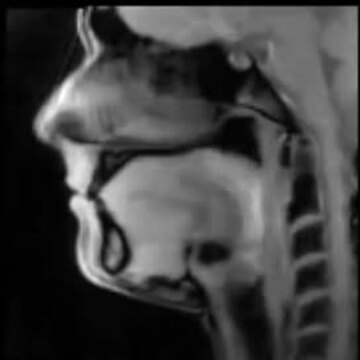

Niesamowite filmy, które pozwalają spojrzeć z innej perspektywy na procesy zachodzące w ciele człowieka, opracowali niemieccy naukowcy z instytutu Maxa Plancka. Zrobili to dzięki nowej technologii "Flash 2", która pozwala w czasie rzeczywistym pokazać obrazowanie metodą rezonansu magnetycznego.

Tak wygląda jama ustna podczas mówienia i śpiewania :